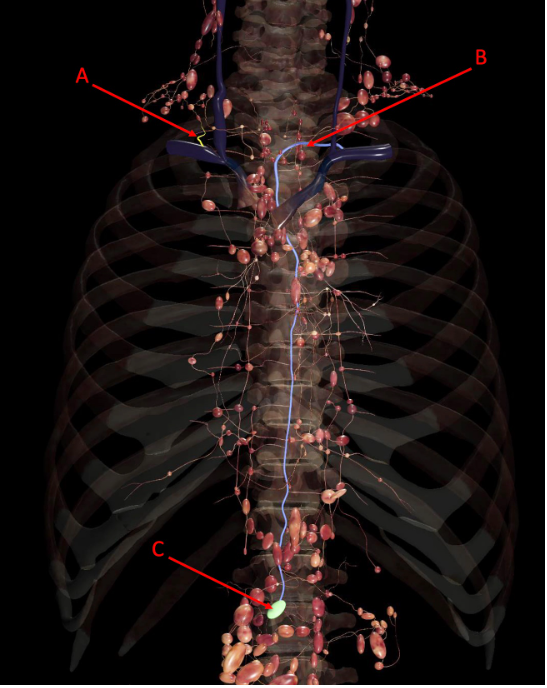

A

A. right lymphatic duct

B. thoracic duct

C. cisterna chyli